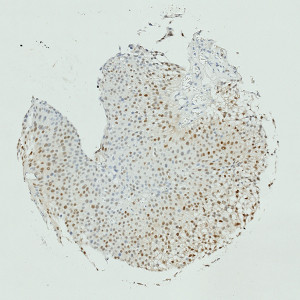

Image of TMA core with bladder tumor tissue after staining by IHC for CyclinD1.

This APP can be used for quantifying the nuclear expression of Cyclin D1. The approach to calculating expression used here, was demonstrated to have a very high correlation to manual scoring in a study involving 300 patients (R2 = 0.85), (publication pending).

The method used for computing the Cyclin D1 expression is started by detecting nuclei using a novel pattern recognition method adapted from Dahl et al, see [6], which is followed by a step that separates adjacent nuclei, see [7]. The detected nuclei are classified as either positive or negative based on a computation of DAB intensity, obtained using color deconvolution.

This leads to the calculation of the positive area fraction, as the area of positive nuclei divided by the total area of nuclei (within the outlined ROI). This is followed by the measurement of the average DAB intensity across all positive nuclei, which is subtracted from 255, to associate higher values with a high staining intensity, which is more intuitive. The expression is then calculated by multiplying the intensity with the area fraction.